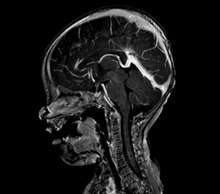

An AVM diagnosis is established by neuroimaging studies after a complete neurological and physical examination.[3][4] Three main techniques are used to visualize the brain and search for AVM: computed tomography (CT), magnetic resonance imaging (MRI), and cerebral angiography.[4] A CT scan of the head is usually performed first when the subject is symptomatic. It can suggest the approximate site of the bleed.[1] MRI is more sensitive than CT in the diagnosis of AVMs and provides better information about the exact location of the malformation.[4] More detailed pictures of the tangle of blood vessels that compose an AVM can be obtained by using radioactive agents injected into the blood stream. If a CT is used in conjunctiangiogram, this is called a computerized tomography angiogram; while, if MRI is used it is called magnetic resonance angiogram.[1][4] The best images of an AVM are obtained through cerebral angiography. This procedure involves using a catheter, threaded through an artery up to the head, to deliver a contrast agent into the AVM. As the contrast agent flows through the AVM structure, a sequence of X-ray images are obtained.[4]